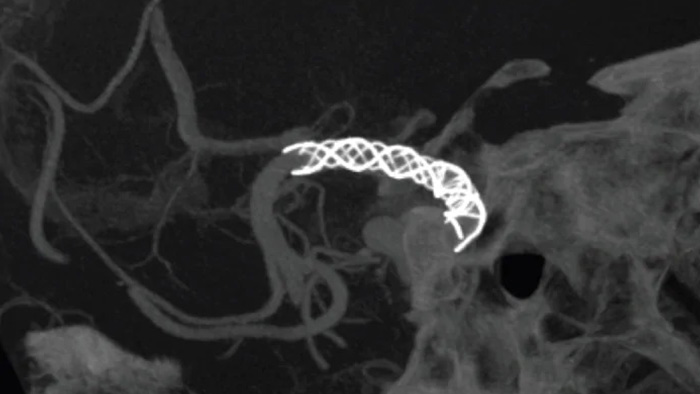

Melhorar a visualização de stents endovasculares, flow diverters e outros dispositivos, bem como a morfologia do vaso até o nível de perfurador com SmartCT Vaso. Esta técnica de aquisição baseia-se num exame de TC de feixe cónico e numa injeção de contraste intra-arterial. É cada vez mais utilizada para o acompanhamento de aneurismas tratados com stents de flow diverter para verificar o posicionamento do dispositivo.